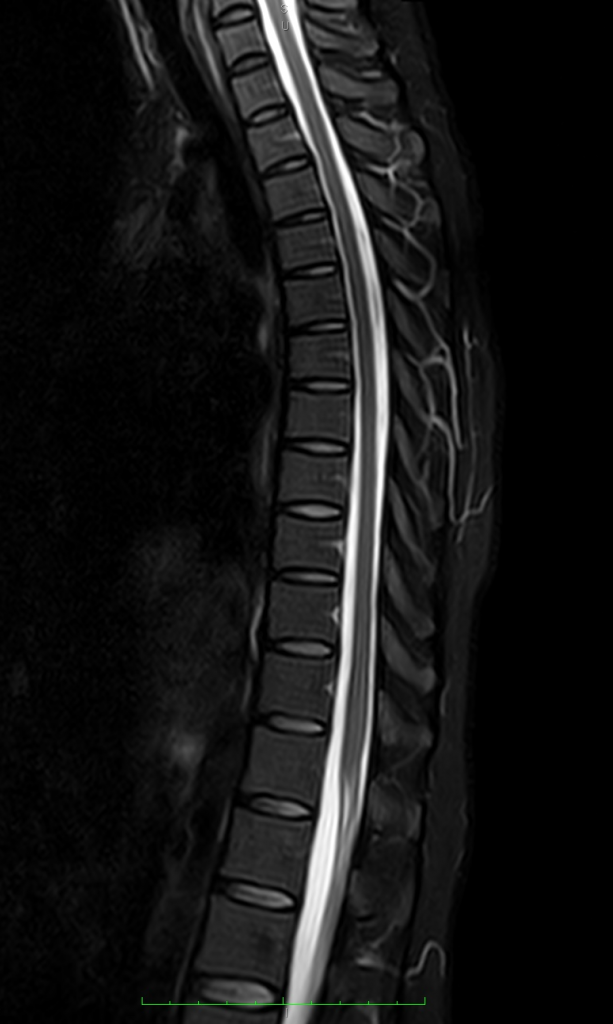

High Quality Images in high vision field

Lumbar Region Fat suppression Images

Clinical Images